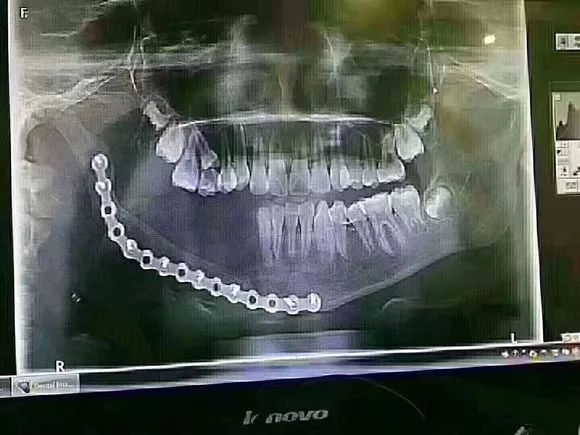

北京一个12岁的孩子,因乳牙过早龋坏,太严重引起下颌大面积囊肿没办法治疗,做了下颌骨切除手术,缺失半侧恒牙,这一生要做无数次假牙!而且孩子面部发育也会受到很大的影响!